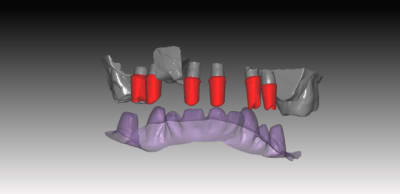

donc voici comme promis piliers ZR sur base Titan

passivité total de l'armature , les piliers sont tous réglés , parallélisés lors de la modélisation de l'ensemble . l'usinage des piliers et de l'armature ce fait séparement pour encore qualité d'ajustage..

Dans le ce cas present Strauman BL 3.3 rc

collage des base titan avec du multilink automix

ce cas est en cour de réalisation , essayage de l'ensemble

déja validé ... je n ai pas de eu de photos , aucun blanchiment de gencive , merci l'ajustage des profils d'émergence dans le soft qui est vraiment bien fait ..

le ptit dernier pour la route

IMPLANT NB REPLACE

nouveauté du system . 2 ccZR transvissées SOLIDARISEE sans base titan

sur des connections interne....

J insiste sur la possibilité et l'avantage de régler les profils d'émergences . de un, on epouse parfaitement la gencive sans trop la mal traiter , et de 2 l'aspect final des couronnes s'en ressent car on a beaucoup moins cet effet de cintrage au collet de la dent qui souvent donne des etrangetées morphologique .

Vous pouvez voir également le puit ( en occlusal)qui depasse de la structure et qui epouse la morpholgie de la ceramique à venir .. assez sympa et bien pratique pour vous lors du rebouchage avec le compo ...